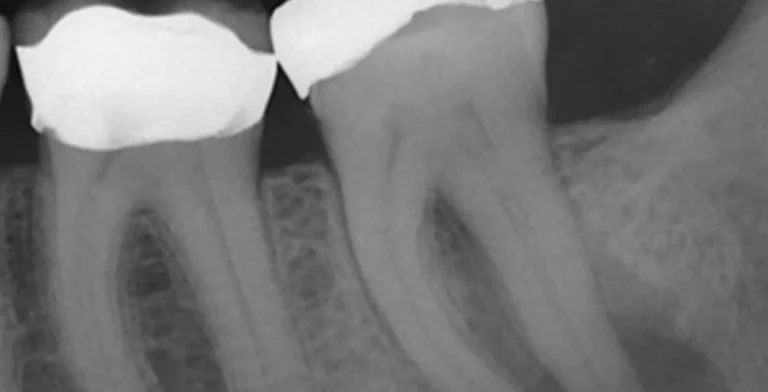

endo-ba04-before-treatment-vitrin-clinic endo-ba04-after-treatment-vitrin-clinic

endo-ba03-before-treatment-vitrin-clinic endo-ba03-after-treatment-vitrin-clinic

endo-ba02-after-treatment-vitrin-clinic endo-ba02-before-treatment-vitrin-clinic

endo-ba01-after-treatment-vitrin-clinic endo-ba01-before-treatment-vitrin-clinic